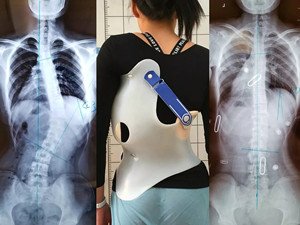

脊柱側(cè)彎是指脊柱的一個或數(shù)個節(jié)段向側(cè)方彎曲,并伴有椎體旋轉(zhuǎn)的三維脊柱畸形。

在青少年快速發(fā)育期內(nèi),身體長得越快,脊柱側(cè)彎的進(jìn)展就越快。矯形支具通過長時的反向矯正力將脊柱維持在一個矯正的狀態(tài);然而由于長時間地佩戴支具會導(dǎo)致肌肉萎縮,當(dāng)支具摘除,脊柱側(cè)彎回彈,且患者無法形成成自我矯正力,呼吸功能亦無法得到改善。最好是在穿戴支具的同時,配合體操訓(xùn)練,通過一系列矯正動作以及呼吸訓(xùn)練,平衡肌力,兩者結(jié)合不但可以穩(wěn)定脊柱,且能增加改善機(jī)會。